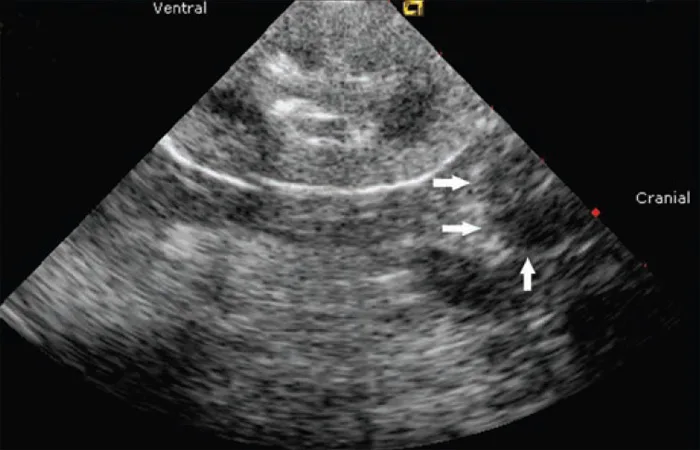

The adrenal mass was consistent with unilateral adrenal hyperplasia or neoplasia (eg, adenoma, adenocarcinoma, pheochromocytoma). Tests that can support a diagnosis of PHA (when available) include measurement of plasma aldosterone and the plasma aldosterone-to-renin ratio.1,2 Recently, measurement of the urinary aldosterone-to-creatinine ratio after suppression with oral fludrocortisone has been reported as a practical confirmatory test for PHA.3 However, when an adrenal mass is identified (Figure 2), surgical excision and histopathology are necessary for a definitive diagnosis and to plan medical versus surgical treatment.

Ultrasound showing a unilateral adrenal mass in a cat (arrows) with a hypoechoic appearance. Courtesy Dr. Edward Javinsky, Veterinary Medical Consultations